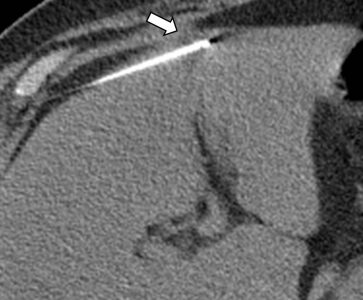

Η διαδερμική βιοψία είναι μια ελάχιστα επεμβατική μέθοδος λήψης υλικού από τον όγκο για κυτταρολογική και ιστολογική εξέταση από εστιακές αλλοιώσεις του ήπατος, του πνεύμονα, του μαστού, του νεφρού κλπ. Συνιστάται από τον κλινικό ιατρό ανάλογα με το είδος και το μέγεθος της βλάβης και πραγματοποιείται με ασφάλεια από επεμβατικό ακτινολόγο συνήθως με την καθοδήγηση αξονικού τομογράφου ή υπερήχων. Στη σύγχρονη ογκολογική θεραπεία, όπου γίνεται προσπάθεια καταπολέμησης του καρκίνου σε μοριακό επίπεδο, κρίνεται αναγκαία η ακριβής ιστολογική ταυτοποίηση του όγκου, ώστε να εφαρμοσθεί εξατομικευμένη θεραπεία για το βέλτιστο αποτέλεσμα.

Σε έναν δεύτερο πυλώνα ογκολογικής θεραπείας η Επεμβατική Ακτινολογία μπορεί να εφαρμόσει τοπικοπεριοχική θεραπεία καταστροφής των καρκινικών κυττάρων με τεχνικές είτε διαδερμικής κατάλυσης (Ablation) είτε διαδερμικού ενδαγγειακού χημειοεμβολισμού (TACE). Στην περίπτωση της κατάλυσης μπορεί να εφαρμοστεί σε καρκινώματα του ήπατος, του νεφρού, των οστών και των όγκων μαλακών μορίων και υπό προυποθέσεις στον πνεύμονα. Παθοφυσιολογικά βασίζεται στην τοπική καταστροφή των καρκινικών κυττάρων με τη δημιουργία ιδιαίτερα υψηλών θερμοκρασιών νέκρωσης εντός του όγκου. Αυτό επιτυγχάνεται με τοποθέτηση ειδικών βελονών-ηλεκτροδίων εντός του όγκου υπό ακτινολογική καθοδήγηση. Τα ηλεκτρόδια αυτά παράγουν υψηλή θερμοκρασία είτε με τη βοήθεια ραδιοσυχνοτήτων (RF ablation) είτε με τη βοήθεια μικροκυμάτων (MW ablation) και προκαλούν πηκτική νέκρωση των καρκινικών κυττάρων χωρίς να επηρεάζουν τα φυσιολογικά κύτταρα.